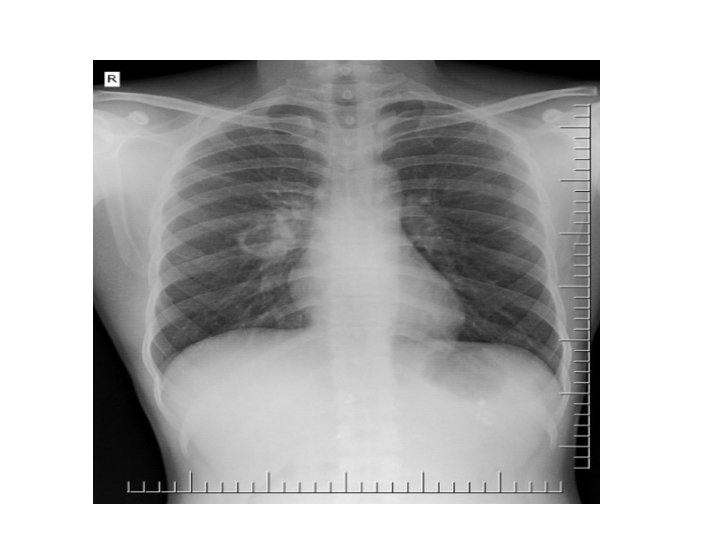

Pneumoperitoneum/ Air under the diaphragm • Erect Chest Xray • Pneumoperitoneum indicates a perforated viscous • Causes : perforated PUD(duodenal ulcer), ruptured appendicitis, typhoid perforation, necrotising enterocolitis, ruptured inflammatory bowel disease, ruptured diverticulitis, bowel cancer, penetrating trauma.

Pleural Effusion • • • Obliteration of the costophrenic angle Obliteration of the cardiophrenic angle Tracheal deviation Meniscus sign Compensatory hyperinflation Causes : heart failure, nephrotic syndrome, cirrhosis, pneumonia, tuberculosis, mesothelioma, bronchogenic CA, SLE, trauma.

Congestive Cardiac Failure • • • Alveolar oedema Kelly B lines Cardiomegally Upper lobe deviation Pleural Effusion